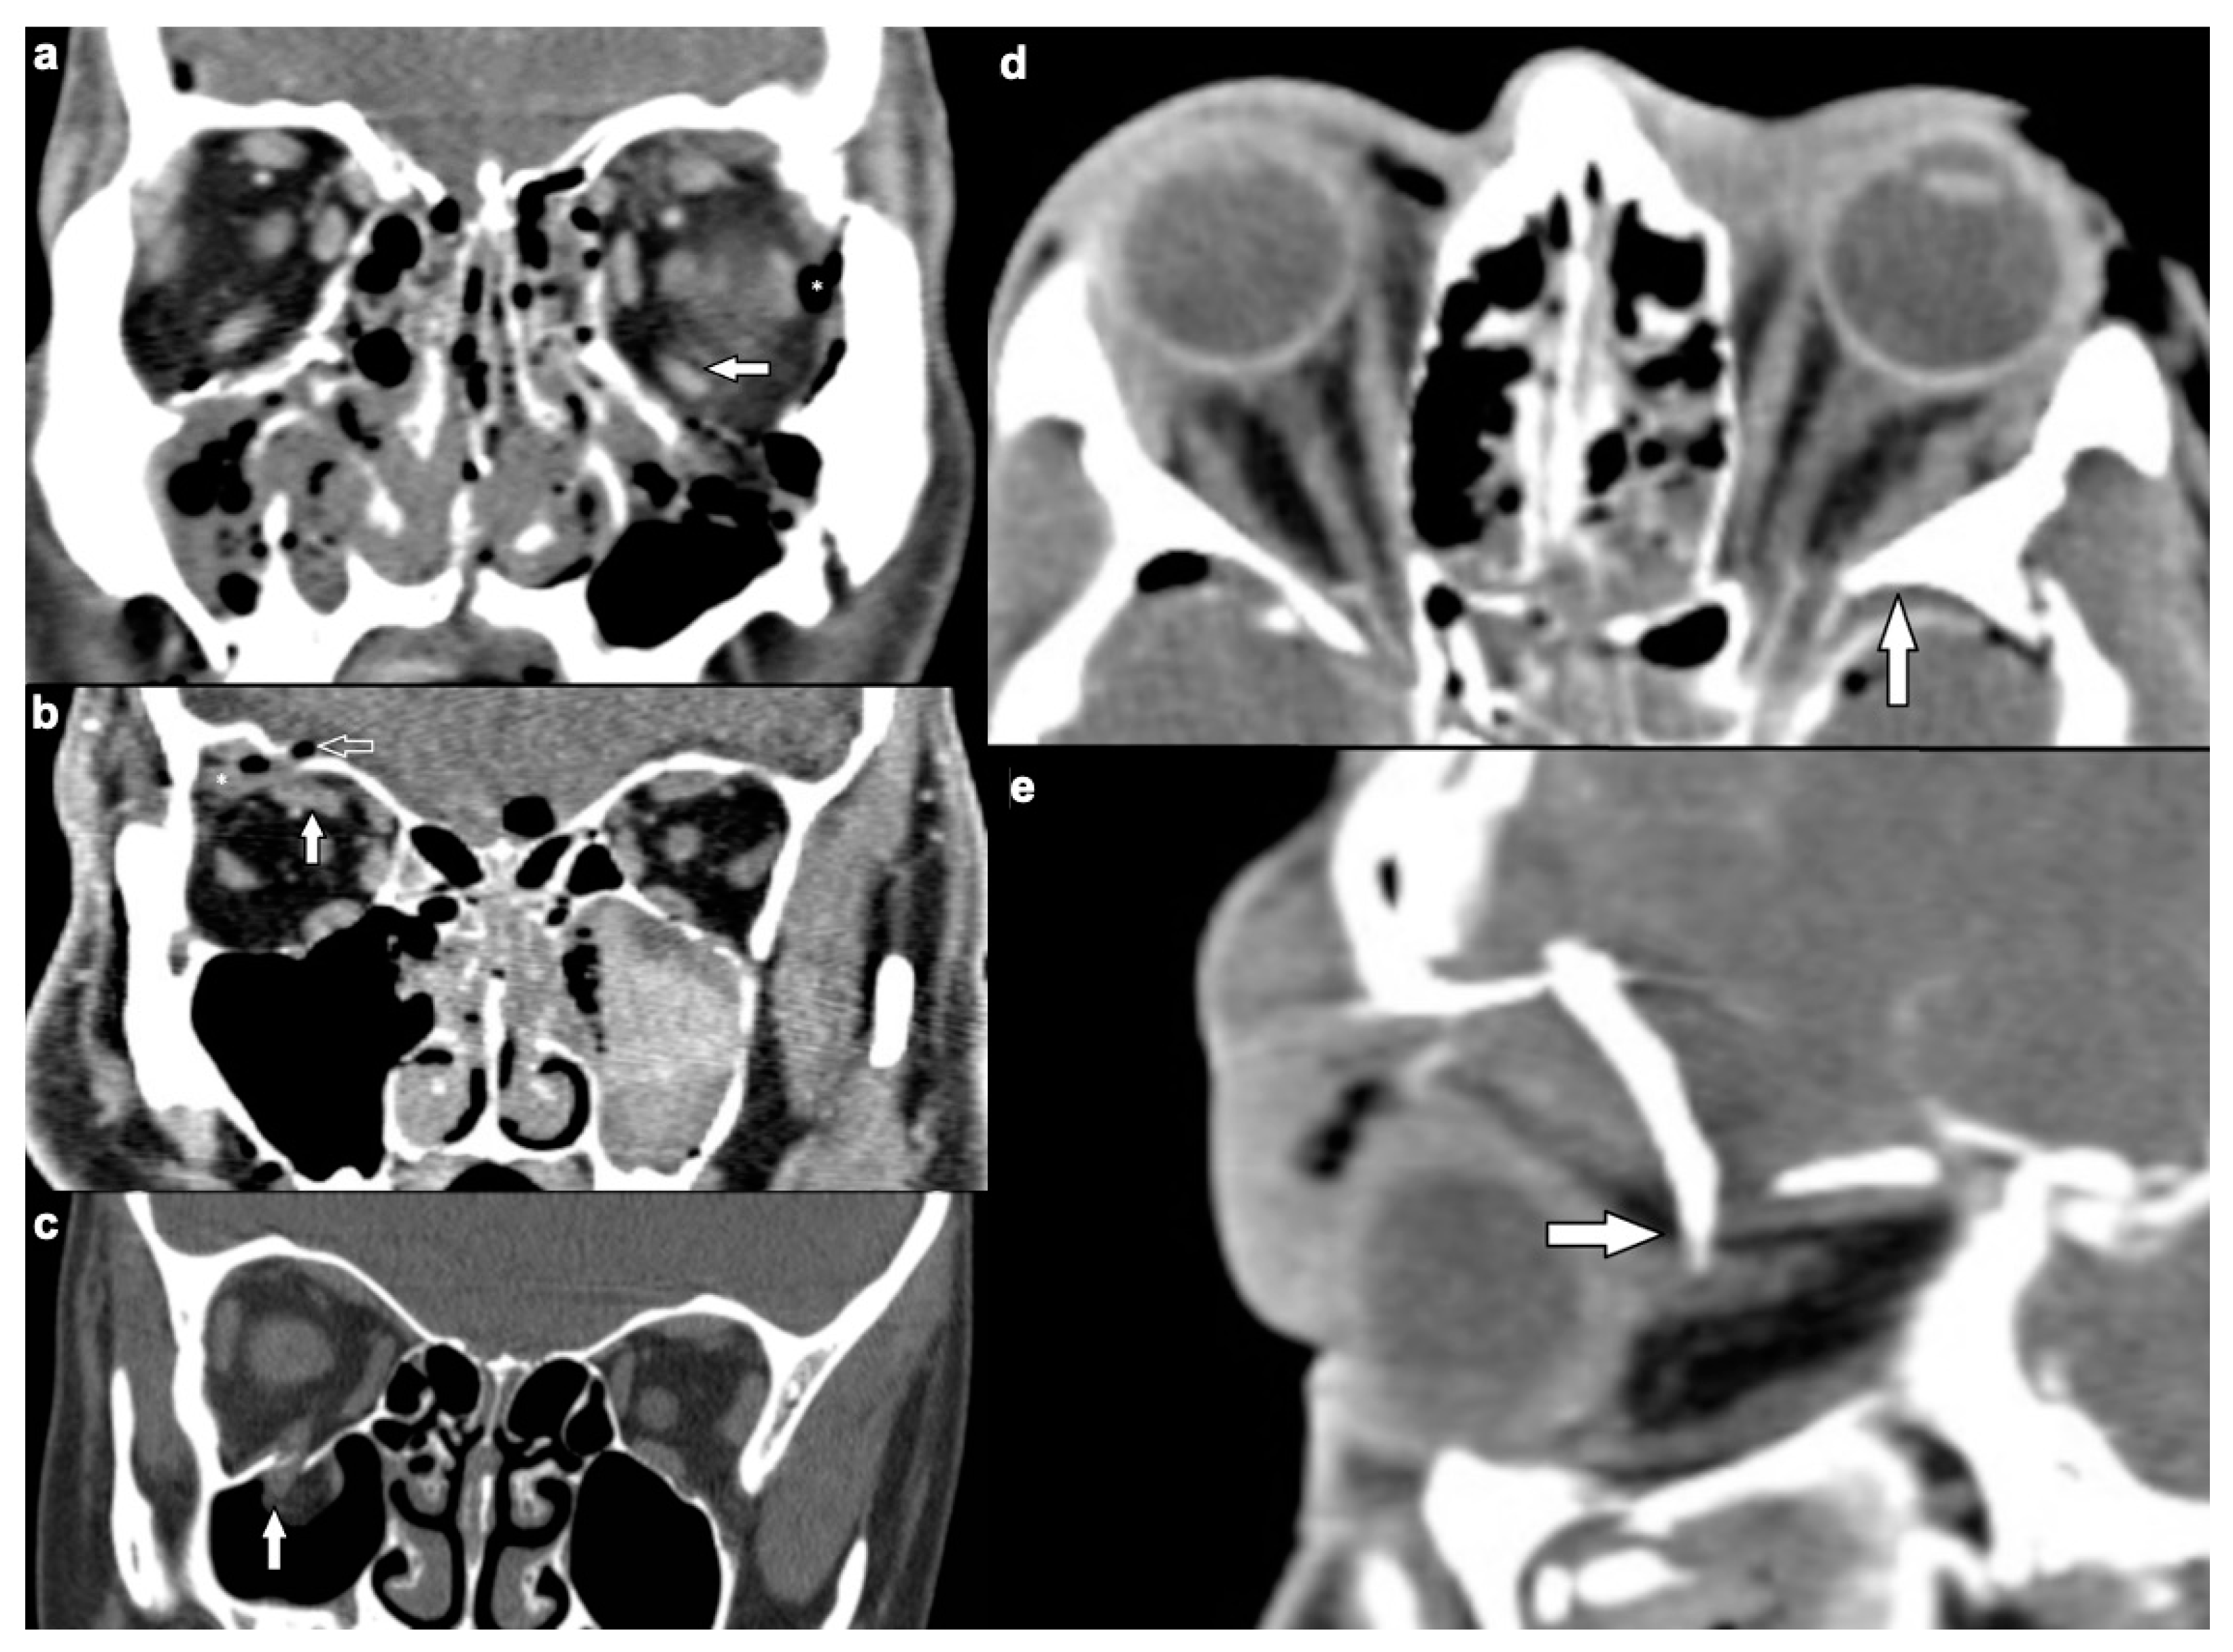

3.2.1. Osseous Injuries

3.2.2. Soft Tissue Injuries

| Location of Soft Tissue Injury | Type of Lesion | n (%) |

|---|---|---|

| Extraocular muscles | 54 (53.5) | |

| dislocation | 45 (44.6) | |

| pierced by bone fragment | 8 (7.9) | |

| intramuscular foreign body | 1 (1.0) | |

| Ocular globe and lens | 38 (37.6) | |

| Deformed globe or vitreous body | 24 (23.8) | |

| rupture of ocular globe | 7 (6.9) | |

| dislocated lens | 6 (5.9) | |

| intraconal foreign body | 1 (1.0) | |

| Optic nerve | 24 (23.8) | |

| elongation | 13 (12.9) | |

| otherwise altered morphology | 10 (9.9) | |

| pierced by foreign body | 1 (1.0) | |

| Orbital vessels | 16 (15.8) | |

| dilated superior ophthalmic vein | 10 (9.9) | |

| direct carotid cavernous fistula | 6 (5.9) |